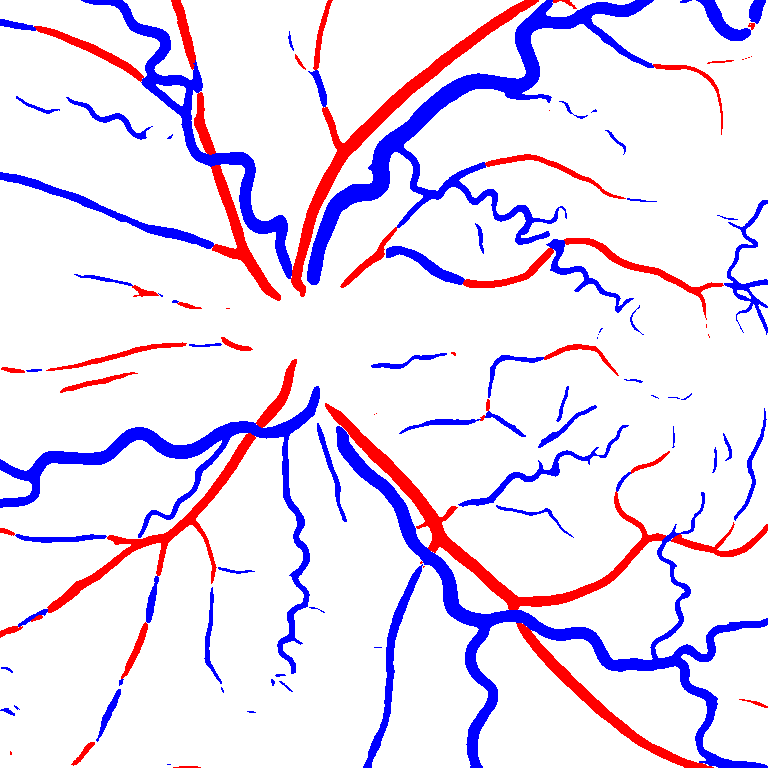

(a) Reference (b) Output (c) Width Map

As reported in Table IV, we compared the SegRAVIR model against competing deep learning-based segmentation approaches on the RAVIR dataset. Evidently, SegRAVIR outperforms these methods as judged by all metrics for artery and vein classes with a healthy margin. In terms of Dice score, SegRAVIR outperforms CE-NET, IterNet and AG-Net by , and for artery segmentation and by , and for vein segmentation, respectively. Fig. 4 presents a qualitative comparison of the semantic segmentation outputs of SegRAVIR, CE-Net, and U-Net. Specifically, SegRAVIR yields more accurate vessel topology (i.e., thickness and orientation) segmentation with higher pixel-wise classification accuracy.

Table VI presents a quantitative comparison of the measured diameters using the segmentation outputs of SegRAVIR and competing approaches. Using the pixel-wise annotated masks, the reference average diameter of the arteries and veins in the test set of the RAVIR dataset were measured as and , respectively. According to our analysis, SegRAVIR can accurately measure the diameter of the vessels and it achieves the smallest MAPE among the competing approaches. Specifically, in comparison to CE-Net, Iter-Net, and DU-Net, respectively, SegRAVIR is on average , and more accurate in terms of MAPE for the measured diameter of arteries and , and in terms of MAPE for the measured diameter of veins. Fig. 6 presents qualitative comparisons of reference and SegRAVIR estimated diameter maps.

(a) (b) (c)

(a) (b) (c)